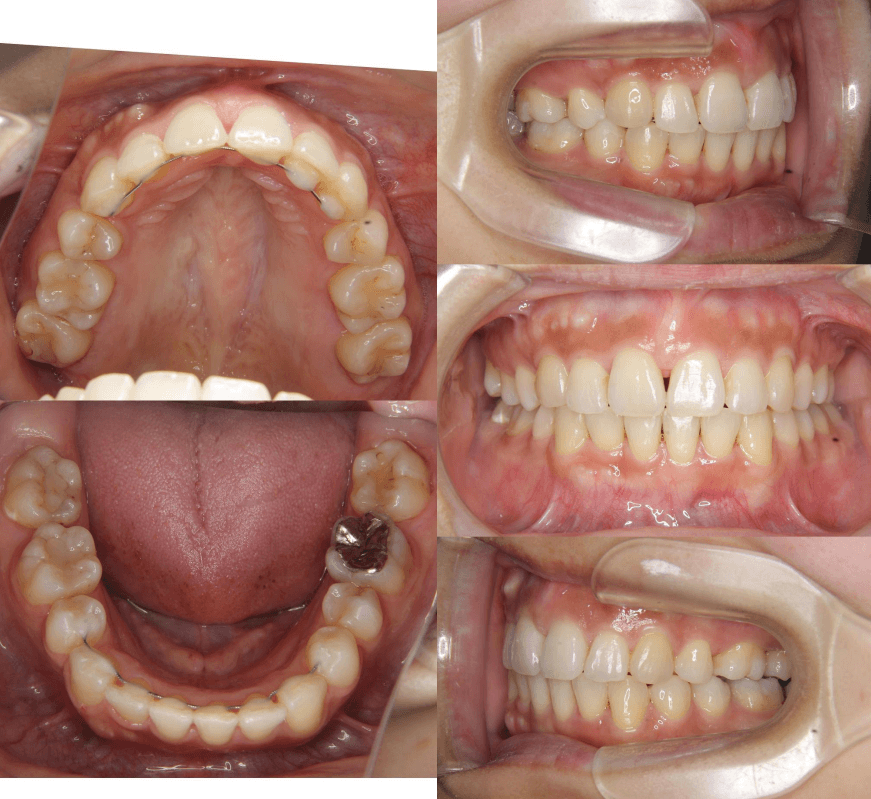

| 年齢・性別 | 25歳女性 |

|---|---|

| 主訴 | 前歯の歯並びの乱れ(叢生)を気にされて来院された25歳女性。咬み合わせや審美的な改善を希望されていました。 |

| 治療期間・回数 | 4年5ヶ月・30回 |

| 費用 | 1100,000円(税別) |